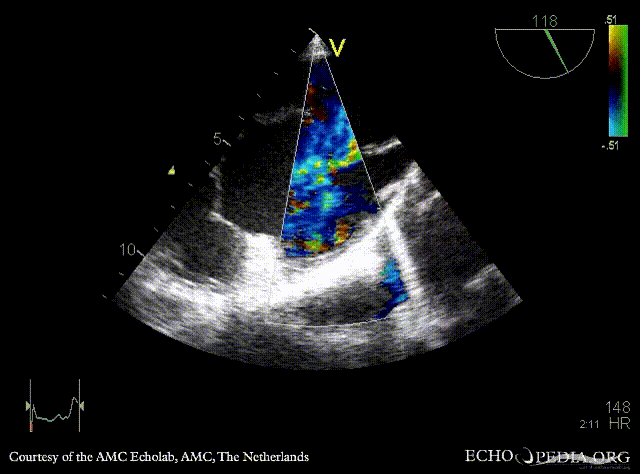

| PSAX: muscular VSD